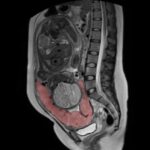

Detection of invasive placenta is important as it necessitates special attention and treatment. A combination of US (anterior placenta) and MRI (posterior placenta) allows for reliable detection and staging. Article: Identification of suspicious invasive placentation...